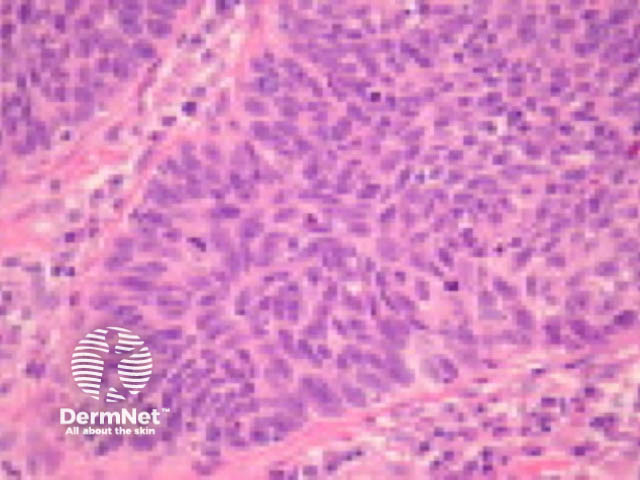

Typical SCC has nests of squamous epithelial cells arising from the epidermis and extending into the dermis (figure 1). The malignant cells are often large with abundant eosinophilic cytoplasm and a large, often vesicular, nucleus. Variable keratinisation (keratin pearls etc) is present (figure 2).

Figure 2